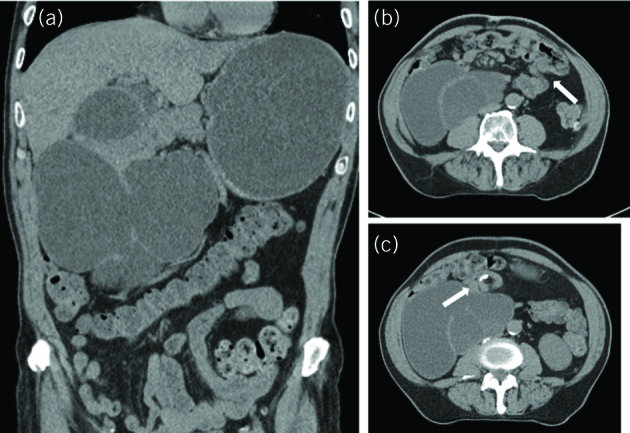

Figure 2.

Non-contrast computed tomography of the abdomen and pelvis; coronal and axial views. (A) There is distention of the stomach and duodenum. The duodenum is located predominantly on the right. (B) The ileocaecal valve (arrow) is shown in the left upper quadrant. (C) Whirlpool sign (arrow) anterior to the dilated duodenum.

Bloods tests on admission showed hyponatraemia, a raised white cell count, and a mildly raised C-reactive protein and amylase. Abdominal and chest x-rays were unremarkable. Non-contrast CT showed a distended and fluid filled stomach and duodenum, with a transition point at the junction of the third and fourth part of the duodenum (Fig 2A). The superior mesenteric vein was to the right of the artery, and the caecum was located in the left upper quadrant (Fig 2B). The whirlpool sign was also noted anterior to the dilated duodenum (Fig 2C). A diagnosis of malrotation was made.